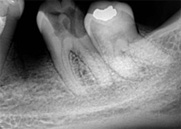

antes depois